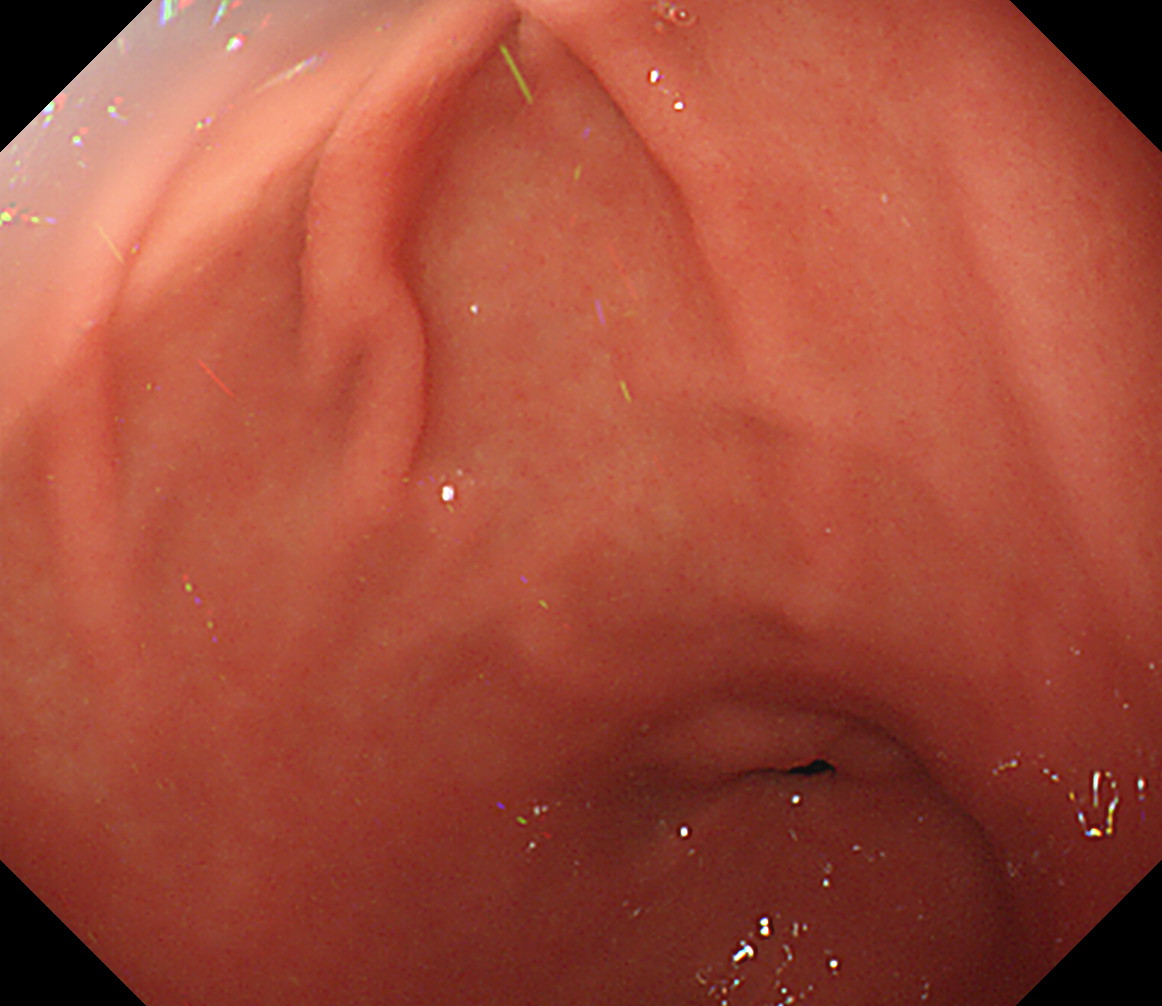

1 食道中部 門歯から約25cm 中部食道

2 食道下部 門歯から約35cm 食道下部